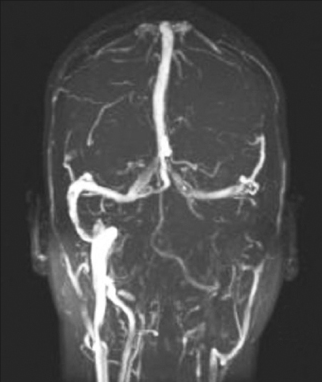

Seema Kapur, MD; Gregory W. Rutecki, MD

<p>2 cases of adults with MRSA infections complicated by left transverse, sagittal cerebral venous thromboses with septic emboli to the lungs and bilateral iliac vein thrombosis,...

02/08/2012